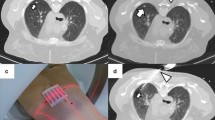

(a–d). CT-guided needle positioning. The patient is in the prone position and the lesion is localized on CT scans. The grid is superimposed on the CT image at the level of anticipated needle entry and the depth of the lesion from the surface is carefully measured (a). Once CT scans have confirmed that the needle tip has actually reached the nodule (b), the deployment of the electrode needle jackhooks within the tumor is assessed both in the axial plane (c) and by using appropriate multiplanar image reconstructions (d).

The electrode needle is advanced through the skin to the proximal edge of the lesion (Fig. 3). Needle advancement still requires careful planning. Even slight degrees of malalignment can cause the tip of the needle to miss the target. This is particularly true for small deep lesions. CT fluoroscopy may be a tool to overcome these difficulties. An increase in resistance is palpable as the needle pierces the lesion. Once CT scans have confirmed that the needle tip has actually reached the nodule, special attention must be placed on verifying the correct placement of the active part of the electrode with respect to the tumor. In fact, unlike in biopsy procedures, a marginal location of the device is not satisfactory. The relationships of the electrode needle with the tumor must be assesed in all the different planes by using appropriate image reconstructions (Fig. 3). When expandable needles with multiple jackhooks are used, it is crucial to check the correct placement of the deployed hooks before starting the ablation.